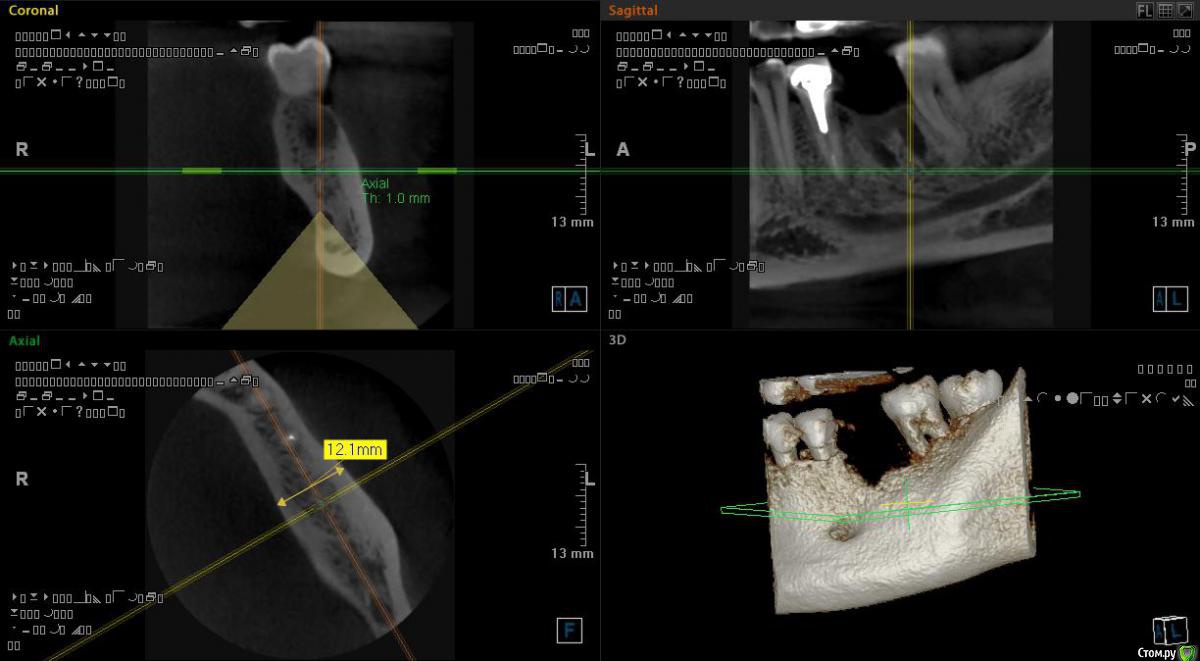

Самарец Опубликовано 11 августа, 2020 Автор Поделиться Опубликовано 11 августа, 2020 срезы выставлены не корректно, покажите еще, в том числе в области седьмого зубаСпасибо за ответ. Так пойдёт? Ссылка на комментарий

Irouil Опубликовано 11 августа, 2020 Поделиться Опубликовано 11 августа, 2020 Все в порядке 1 Ссылка на комментарий